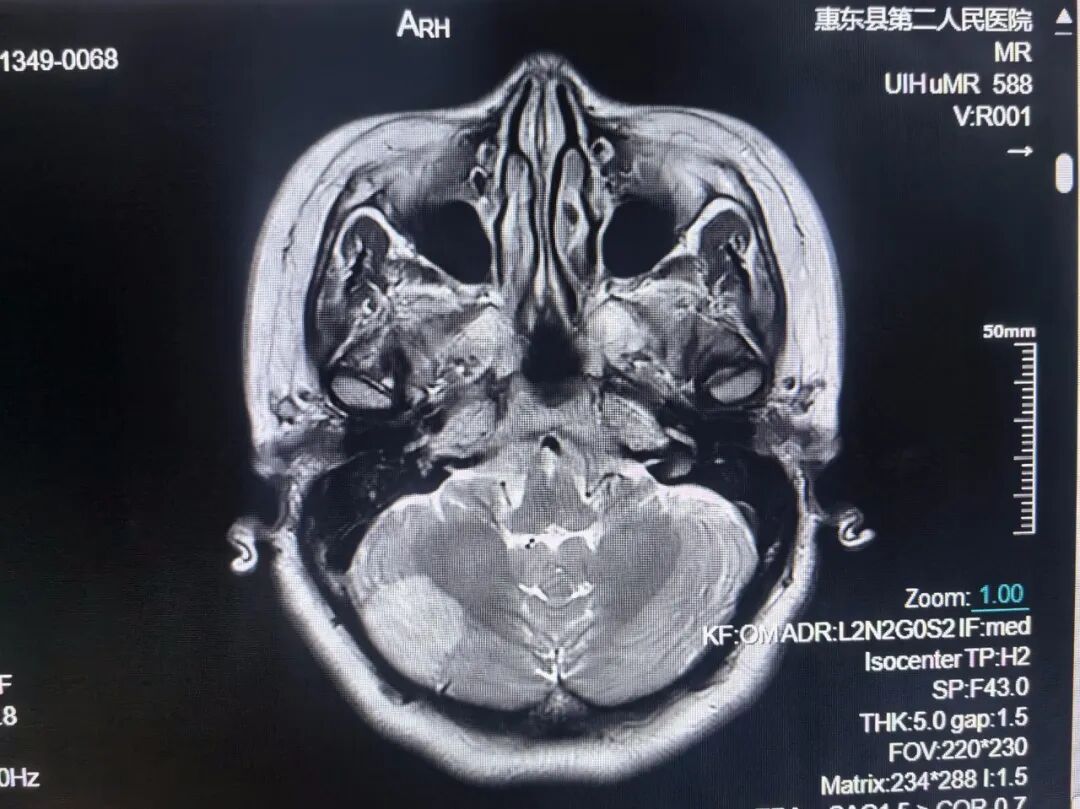

颅脑MRI检查

①先天性颅脑发育异常:包括器官源性畸形和组织源性畸形,MRI可确诊;②脑积水;③脑萎缩;④卒中及脑缺氧:脑梗塞和脑出血等;⑤脑血管疾病:高磁场的MR通过血管成像(MRA)技术显示;⑥颅内肿瘤和囊肿;⑦颅脑外伤;⑧颅内感染和其他炎性病变;⑨脑白质病。

急性脑梗死磁共振成像